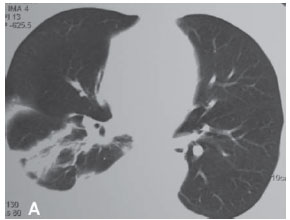

Uma mulher de 63 anos, do lar, não tabagista, previamente hígida, apresentou-se com queixa de aumento de volume em pescoço, face anterior do tórax, abdome e membros inferiores. Havia associação com dispnéia discreta aos esforços. O quadro teve início após atividade física leve em academia de ginástica, havia cinco dias. Negava doença pulmonar prévia e referia uso de fluoxetina a 20 mg/dia, bromazepam a 3 mg/dia e reposição hormonal feminina regular. Ao exame clínico observou-se um discreto aumento de volume em fossa supraclavicular esquerda e face lateral direita do pescoço. Observou-se ainda diminuição do murmúrio vesicular de forma difusa e de frêmito toracovocal em bases (direito maior que esquerdo), além de edema de parede abdominal anterior e de membros inferiores (grau I/IV). Foram solicitados hemograma, coagulograma, glicemia, creatinina, uréia, velocidade de hemossedimentação, colesterol total, HDL, triglicerídeos, T3, T4, TSH e parcial de urina, os quais se apresentaram todos normais, descartando a presença de dislipidemia, coagulopatia, infecção, nefropatia e hipotireoidismo. A avaliação radiológica do tórax revelou um pequeno derrame pleural bilateral (Figura 1), confirmado pela tomografia axial computadorizada de tórax (Figura 2A). Esta foi complementada com cortes ao nível do pescoço, que evidenciaram edema na região supraclavicular esquerda com imagem hipodensa (20 x 10 mm) adjacente ao feixe vasculonervoso do pescoço (Figura 2B). A ultra-sonografia da região cervical mostrou a formação de uma coleção cística, posteriormente aos vasos cervicais, sugestiva da ruptura do tronco jugular esquerdo. Demonstrou ainda um pequeno aumento da espessura do músculo esternocleidomastóideo esquerdo, sugestivo de processo inflamatório secundário a distensão muscular (Figura 3). A paciente foi submetida a toracocentese diagnóstica à direita com obtenção de líquido leitoso compatível com QT. A análise laboratorial demonstrou tratar-se de um exsudato com predomínio de polimorfonucleares e com dosagem de triglicerídeos de 2.035 mg/dl, colesterol de 131 mg/dl e proteínas de 9,7 g/dl, confirmando o quadro laboratorial de QT. Foram realizadas citologia oncótica, bacterioscopia de Ziehl, micológico direto e culturas, que resultaram negativos, descartando processos malignos e doenças infecciosas.

O diagnóstico do QT é laboratorial, pois a clínica e os exames de imagens não o confirmam. A tomografia axial computadorizada de tórax é útil para descartar a presença de linfoma ou metástase, mas não auxilia no diagnóstico de QT. O derrame pode ser tanto do lado direito como do esquerdo, dependendo da altura da lesão do ducto torácico. Lesões abaixo de T5 freqüentemente causam derrame no lado direito e, acima de T5, do lado esquerdo. Também foram descritos casos de derrame bilateral.(10) Assim, o diagnóstico é realizado após toracocentese, pela presença de um líquido branco, com pouco cheiro e aparência leitosa.